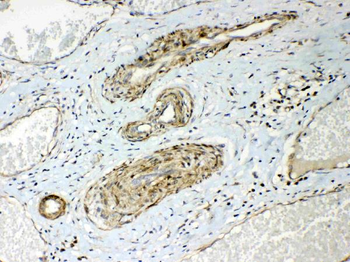

- Anti-GSTM3 Antibody [orb402287]

ELISA, IHC, WB

Human, Mouse, Rat

Rabbit

Polyclonal

Unconjugated

10 μg, 100 μg - Anti-S100 alpha 6/S100A6 Antibody [orb315184]